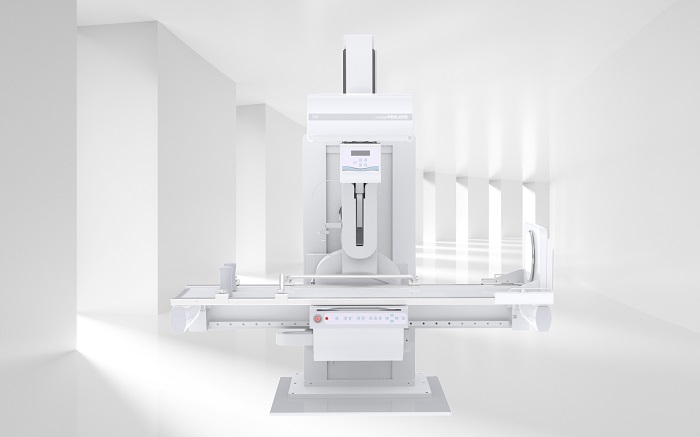

普利德動態平板DRF采用大尺寸高清動態平板探測器,可為臨床提供大幅面高清圖像,全面滿足數字攝影、透視、造影及可視化高清點片等多種臨床應用需求。獨特實用的升降床配合智能靈活的機械多維運動,輕松滿足各類特殊體位、各角度拍攝需求,實現高質量拍片、高幀率透視以及便捷高效的臨床操作,滿足醫療機構多樣化檢查需求。

普利德動態平板DRF床體智能化程度更高,在進行子宮輸卵管造影檢查時,醫生可以通過調整床體起倒角度精準控制造影劑的流動方向和速度,并根據造影劑在輸卵管及盆腔里的顯影準確判斷輸卵管堵塞部位、程度及性質,極大提高了拍片效率和診斷的精準性。